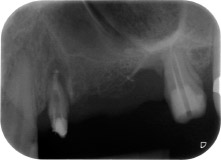

A 58-year-old female patient complained of pain and increased mobility of her bridge abutment tooth 24. Periodontal inflammation was present with pocket depths of 7 mm mesiobuccally and more than 12 mm distally, as well as third-degree furcation involvement. Moreover, the radiograph revealed an extensive periodontal lesion around the apical region of the (alio loco) endodontically pretreated tooth 24 (Fig. 1).

One month later, on the day of surgery, pain and inflammation at tooth 24 were minimal, but mobility of Miller class 2 was still present. After opening the flaps and cleaning the periapical and peri radicular infected tissue, the extent of the bone defect became obvious (Figs. 2 and 3).

At the buccal root, all vestibular and distal bone was missing. Attachment was essentially restricted to the palatal root, underlining the preliminary poor prognosis. Tooth 27 also showed a reduced horizontal attachment and a minimal apical rarefaction (cf. Fig. 1) without clinical symptoms.